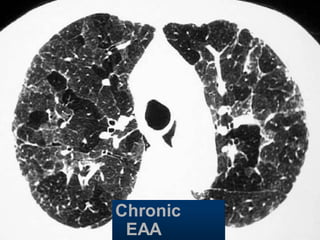

EAA

Hypersensitivity pneumonitis

Extr. Allerg. Alveolitis (EAA) HRCT

Morphology

chronic: fibrosis

Intra- / interlobular septal thickening

Irregular interfaces

Traction bronchiectasis

acute - subacute

acinar (centrilobular) unsharp densities

ground glass (patchy - diffuse)